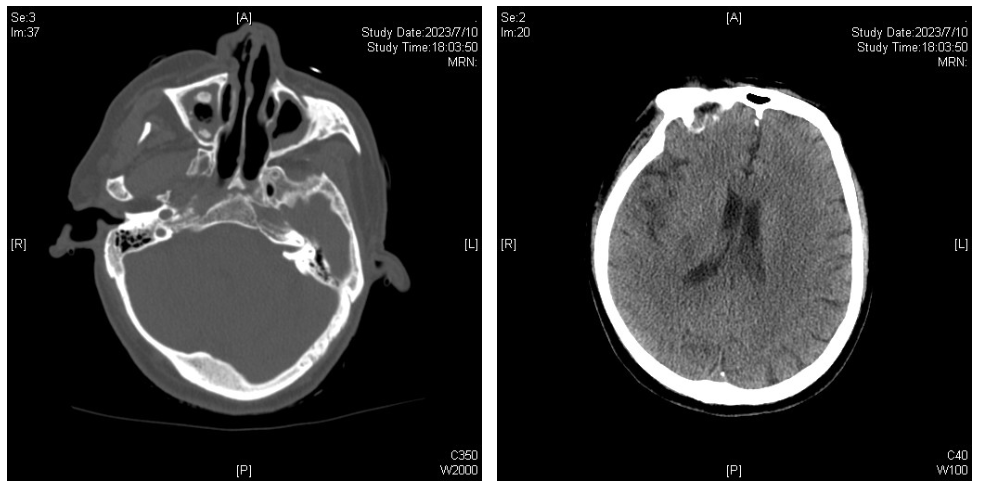

患者于7月10日上午出现口齿不清,但对答切题,无肢体活动障碍等。下午出现嗜睡,左侧肢体活动度较右侧差;伴气促加重。头颅CT:脑实质未见异常密度,双侧上颌窦炎,真菌感染可能。胸部CT:双肺感染较前加重,左上肺舌段、双下肺实变,双侧胸腔少量积液。

图8. 头颅CT(2023-07-10)

图9. 胸部CT(2023-07-10)